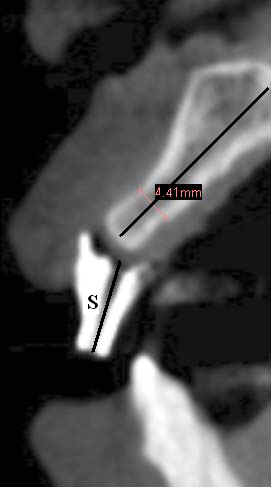

Fig.6 (magnification) The long axes of the drill sleeve (S) and of the alveolar ridge are not aligned.  Back to main text